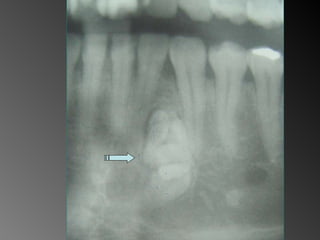

Exame complementares RadiografiaPanorâmica; Radiografia Oculsal; Teste de Vitalidade; Punção Exploratória; Biópsia incisional.

Teste de VitalidadeDente 43: Negativo Dentes 42,44 e 45: Positivo.

Exame complementares Radiografia Panorâmica; Radiografia Oculsal; Teste de Vitalidade; Punção Exploratória; Biópsia incisional.

Teste de Vitalidade Dente 43: Negativo  Dentes 42,44 e 45:  Positivo.